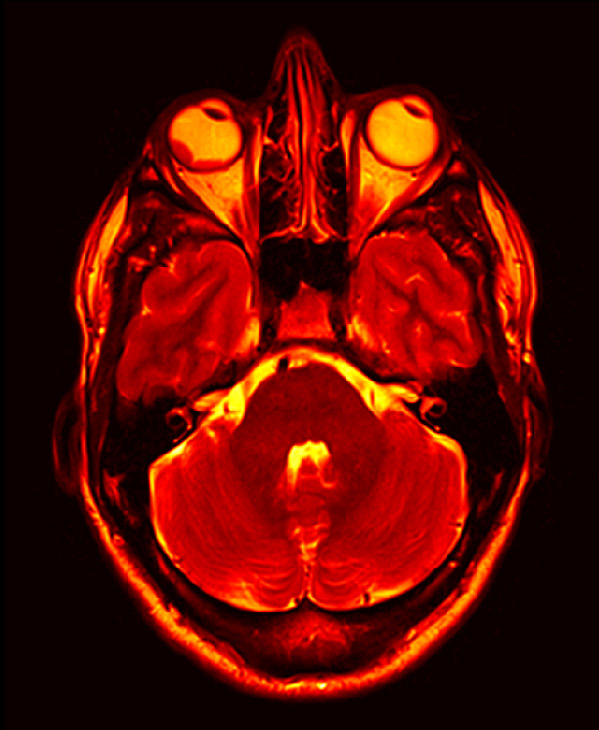

emDOCs.net – Emergency Medicine EducationApproach to the Red Eye